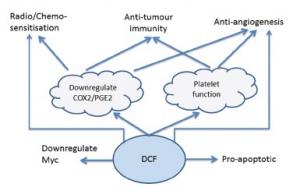

VOLTARÈNE (diclofénac): Un anticancéreux prometteur?